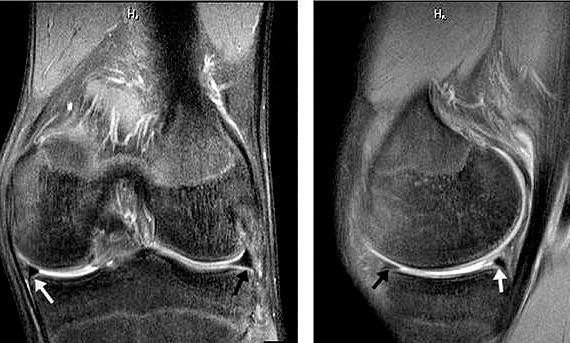

但如果在过度的暴力伤害、长时间的使用等诱因下 , 半月板可以发生损伤 , 半月板的形态发生了改变 , 也就是半月板发生了撕裂 , 这种情况我们称之为半月板的三度损伤 , 在核磁上 , 我们可以比较明确地发现半月板的损伤信号 , 这种信号在核磁上往往表现出来水肿的信号 , 在核磁的某些条件下显示出来的是高亮的信号 , 比如下图当中箭头所示的部位就是一个线性的高亮信号 , 提示半月板发生了分层撕裂 。 这种高亮的信号往往代表着半月板撕裂周边出现了水肿 , 或者半月板的撕裂部位内有关节液渗入 。

第一 , 增加患者经济负担 , 毕竟核磁检查费用是比较高的 , 频繁的、反复的进行核磁检查真的会增加有一些患者的负担 , 尤其是在一些经济欠发达的地区 。 本人所在的地区经济就是欠发达地区 , 建议患者做核磁非常的困难 , 更不要说术后反复的复查了 。 第二 , 核磁报告经常会提示“损伤信号”这样的结果 , 很多患者看到核磁报告单以后 , 会拿着报告单质问医生是不是手术没给做好 , 怎么做完了手术 , 核磁还显示有损伤信号 , 很容易发生医患之间的纠纷 , 有的时候 , 再解释也于事无补 , 因为患者已经认定了手术没有做好 。 那么为什么在复查的核磁结果上会有损伤信号呢 , 其实很简单 , 这就是由于手术本身也会造成半月板以及周边结构的水肿 , 在核磁影像上有些序列也是高亮的 。 而手术和真正的损伤在影像学上的的高亮信号并没有任何的区别 。 比如在下图的右侧箭头当中可以看到一些小的发亮的信号 , 这种情况往往在报告单上会被提示为:可见损伤信号 。 所以有些患者要求复查核磁时 , 本人会提前告诉患者 , 有可能会出现这种情况 , 打好预防针 , 患者就不会有太冲动的表现 。 其实 , 对于术后的患者来讲 , 在进行关节镜手术的时候 , 已经最直观的看到了患者的损伤 , 已经进行了处理 , 在术后的复查当中 , 主要还是要依靠医生的查体以及患者的症状 , 如果没有特殊的症状 , 也没有特殊的查体表现 , 其实没有必要复查核磁 。